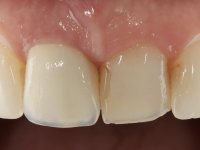

52-year-old female patient, non-smoker. He used an appointment with an implant already placed in the 1.1 site. It was provisionally rehabilitated with a composite resin crown adhered to the palatal surface of the adjacent teeth. This provisional had taken off several times in the last month, even in this first consultation it was taken off. We took advantage of this situation and verified that the “Tissue Level” implant had 2 to 3 mm of prosthetic space available. A deep bite and the inclination of the long axis of the implant posed a very difficult situation for the rehabilitator. If one chooses a abutment with a cemented crown, the height of the abutment would be minimal, with no retention or resistance. If a screwed solution is chosen, the screw access hole would emerge through the vestibular surface. It should be remembered that in 2006 the prosthetic solutions for this situation were limited to these options: 1- Screw-retained angled metal abutment for cemented crown 2 - Screw-retained angled metal abutment for transversally screw-retained crown 3 – Syn Octa metal abutment for screw-retained crown. A serious problem in this rehabilitation was guessed right from the start. The patient had a thick gingival phenotype and good oral hygiene.

After the impression of the implant using a double-mix technique with double viscosity and the collection of shape and color information by the ceramist, we proceed with the work. In the model, a syn octa was placed over the implant, and a screw was placed on it to assess its emergence in relation to the incisal edge. Then, an adequate emergence profile in the artificial gingiva was prepared. A abutment with characteristics suitable for overbite and simultaneously capable of receiving a veneer was waxed on top of this scenario. This waxing gave rise to the manual milling of a very personalized abutment. An infrastructure in Zr was also made for the veneer with a very great adaptation to the abutment. On this infrastructure ceramics were placed. Ceramic fluorescence sought to compensate for the lack of fluorescence that Zr had and obviously further customize the aesthetics. The adhesive bridge was removed and the definitive work was placed. The syn octa was initially tightened with 35 N to the implant and then the Zr abutment was tightened over the syn octa with 15 N. The access hole was plugged and then the veneer was cemented with resin-reinforced glass ionomer. After 15 years, the patient returned to the consultation with tooth mobility. Fortunately, nowadays we have the possibility of having dynamic tightening wrenches that allow tightening screws with greater inclinations. An access cavity was made without damaging the incisal edge of the veneer. Tightening was done with a dynamic wrench with 15 N torque. The hole was covered with Teflon and filled with composite resin. This solution allowed the problem to be solved in a simple and economical way.